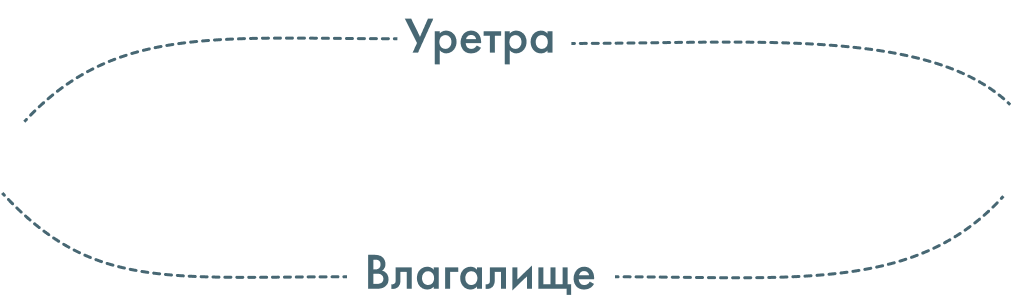

- смещение (эктопия) наружного отверстия уретры к входу во влагалище, а иногда даже на его переднюю стенку. Может сопровождаться недоразвитием и укорочением уретры;

Гипоспадия у женщин